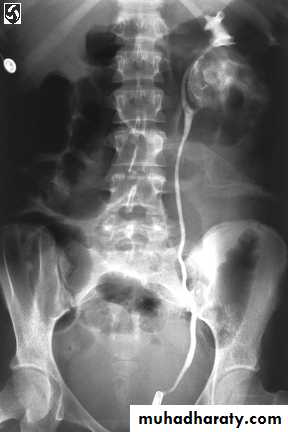

KUB: Renal calcification

IVU

CXR